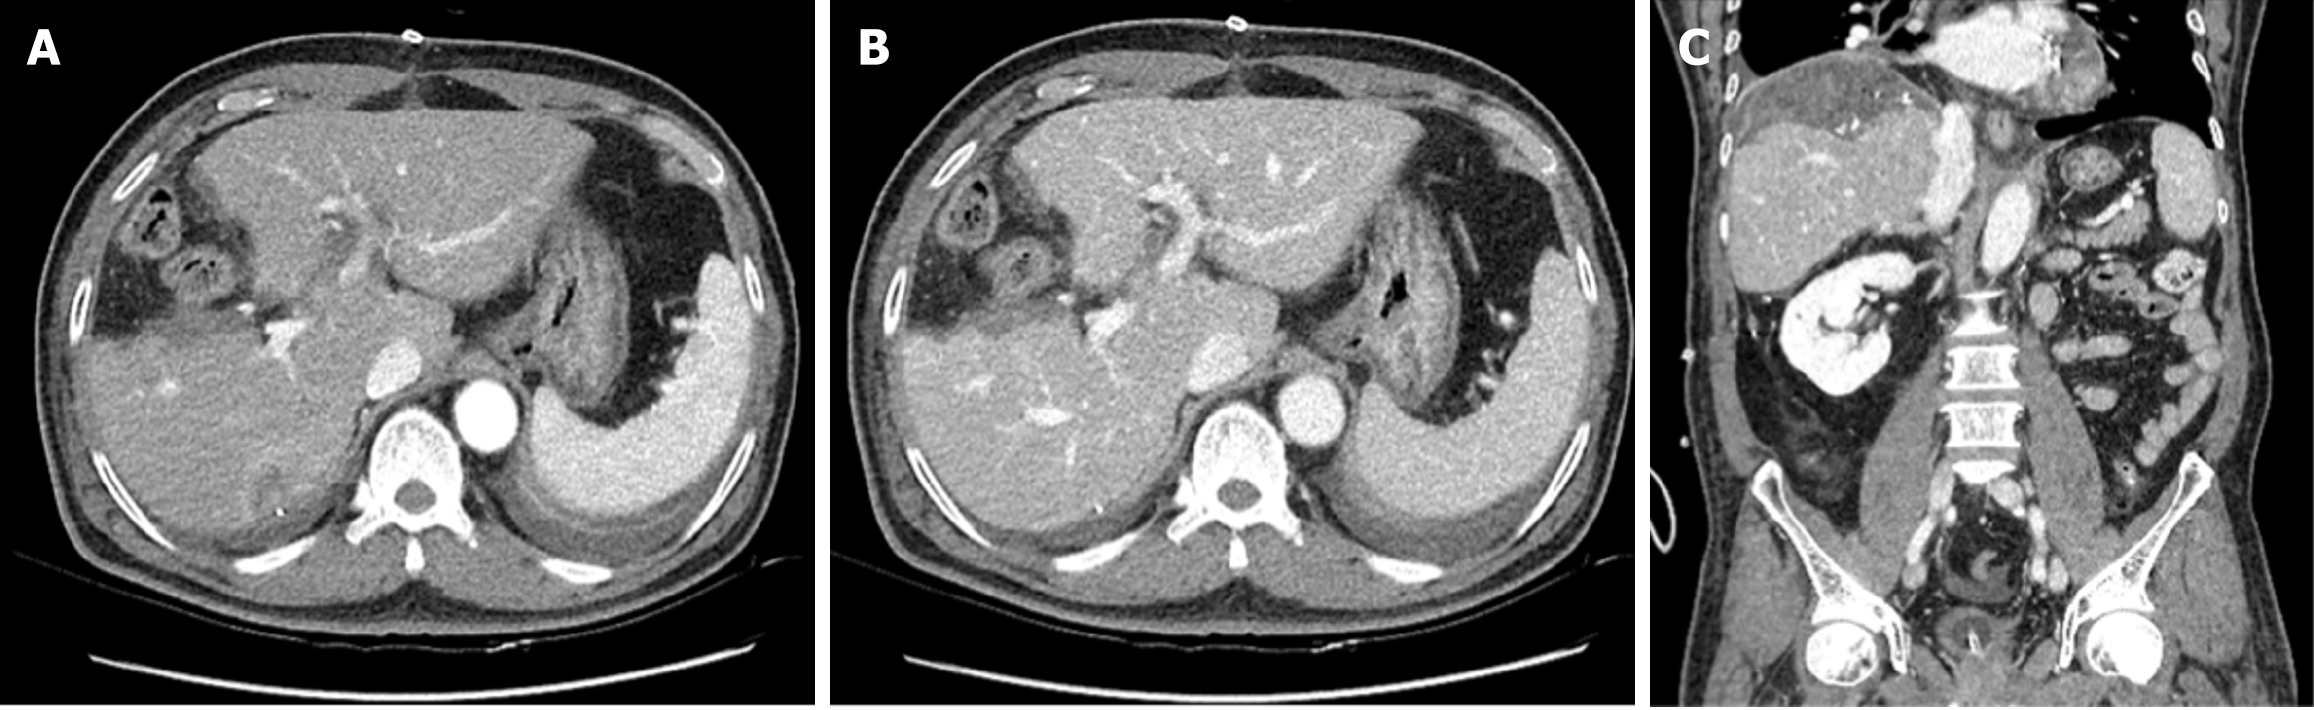

On postoperative day 5, follow-up abdominal dynamic CT revealed typical postoperative changes after laparoscopic anterior sectionectomy (Figure 4).

Following discharge, the patient was monitored with regular follow-ups, including CT and laboratory tests, performed every 3-4 months during the first year and subsequently at 6-month intervals. Over the 3-year follow-up period, there was no evidence of liver recurrence or postoperative complications (Figure 5), and the patient remained in good health.